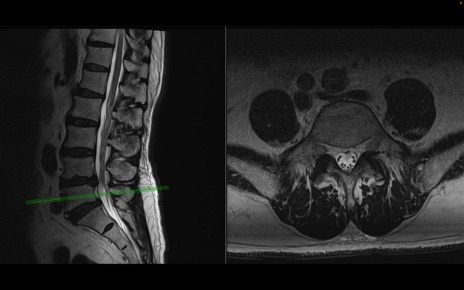

【整形】TIPS症例2 腰椎MRI 横断像と矢状断像

【症例】70歳代男性

【主訴】左下肢痛

【現病歴】2週間前くらいから腰痛、左下肢痛あり。左臀部から大腿、下腿外側のしびれが常時ある。歩行とともに同部位の痛みあり。

【身体所見】Lasegue70-/60+、Bragard-/±、PTR ±/±、ATR -/-、IP 5/5、TA 5/4、TS 5/5、EHL 右第1足趾なし/3、FHL 5/5、hypersthesia(-)、足背動脈触知良好

異常所見と診断は?